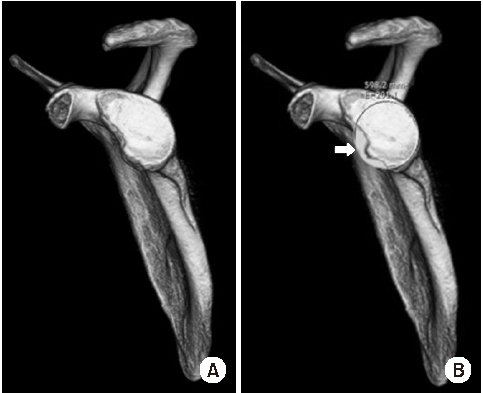

Shoulder joint dislocation has the most common incidence rate compare compared to other joints. It is reported that shoulder Shoulder dislocation couldmay be associated with glenoid rim, greater tuberosity of humerus and coracoid process fracture. There were have only been 2 cases of anterior shoulder dislocation simultaneously combined with simultaneous glenoid rim, coracoid process, and humerus greater tuberosity fracture worldwide and no report reports in Korea. We present a case of quadruple fracture (glenoid rim, coracoid process, greater tuberosity, surgical neck of humerus) associated with anterior shoulder dislocation and treated successfully by open reduction. In addition, with we provide the injury mechanism, diagnosis, treatment procedure and discussion.